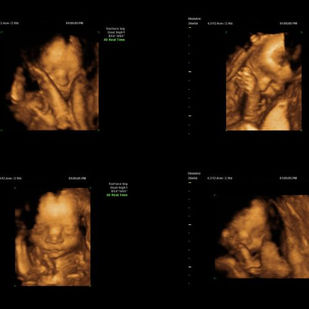

È possibile effettuare, in primis, valutazioni annuali per prevenzione, giungere alla nostra attenzione per approfondite ecografie di secondo livello, una volta riscontrata un’anomalia o eseguire esami ecografici per valutazioni specifiche (morfologia di cavità uterina e tube) ad esempio in donne desiderose di prole. Non ultima la possibilità di eseguire ECOGRAFIE GINECOLOGICHE 3D, all’avanguardia negli ultimi anni.